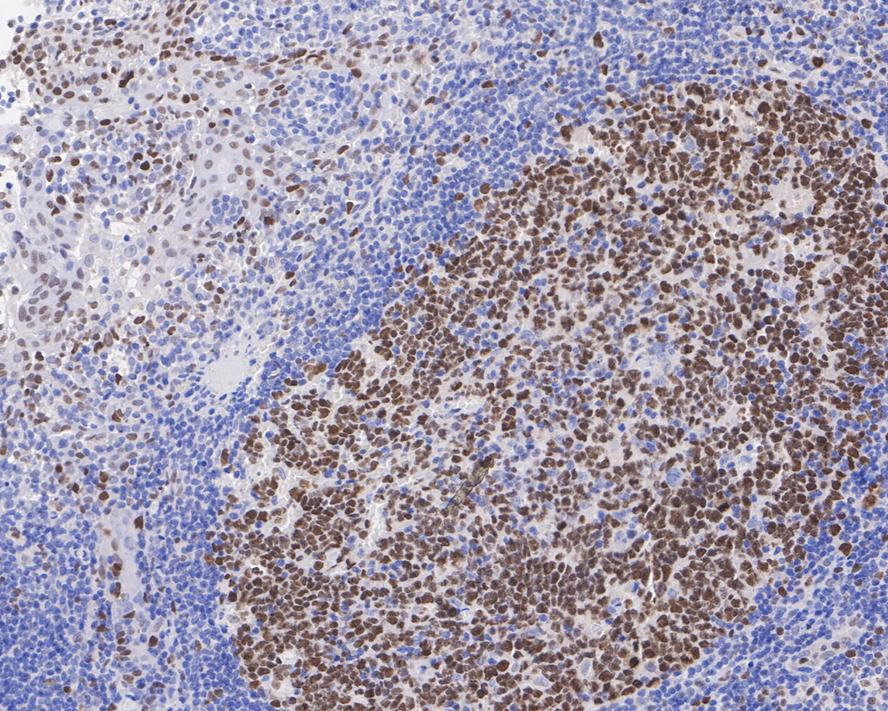

Immunohistochemical analysis of paraffin-embedded human tonsil tissue with Rabbit anti-KMT6 / EZH2 antibody (ET1701-56) at 1/500 dilution.

The section was pre-treated using heat mediated antigen retrieval with Tris-EDTA buffer (pH 9.0) for 20 minutes. The tissues were blocked in 1% BSA for 20 minutes at room temperature, washed with ddH2O and PBS, and then probed with the primary antibody (ET1701-56) at 1/500 dilution for 1 hour at room temperature. The detection was performed using an HRP conjugated compact polymer system. DAB was used as the chromogen. Tissues were counterstained with hematoxylin and mounted with DPX.